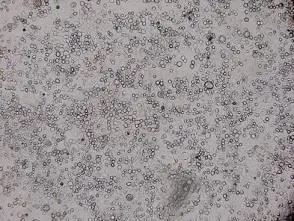

從所示HEp-2細胞相片觀察:

- 大量細胞呈現圓形且高度折射(refractile),明顯脫離基底單層,留下空洞區。

- 無可辨識之巨型多核融合細胞(syncytia)或嗜酸性核內包涵體。

- 細胞形態與典型ballooning degeneration相似,說明細胞受到快速破壞後脫落。

HSV感染HEp-2細胞,感染後約8–12小時即產生CPE,表現為細胞圓形化(ballooning)與脫落,少數可見syncytia,但以單一圓形脫落細胞為主(pmc.ncbi.nlm.nih.gov)。與影像吻合。 -

此HEp-2細胞影像呈現大量圓形、折射細胞快速脫落,未見典型RSV syncytia或adenovirus包涵體,符合HSV所致ballooning degeneration特徵且發生時間短。臨床上病患口唇周圍水泡亦最常因HSV感染所致,因此正確答案為單純疱疹病毒(選項C)。